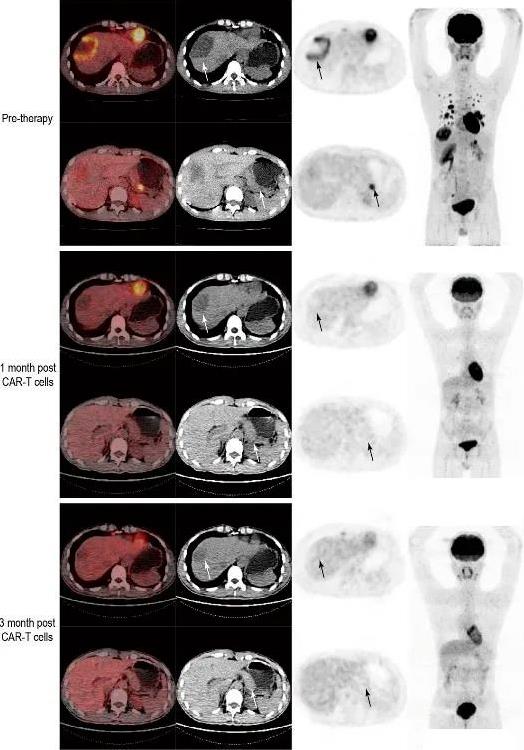

图1 1级剂量组CRC-03-08患者的治疗情况

▲图源“ESMO Congress 2023”,版权归原作者所有,如无意中侵犯了知识产权,请联系我们删除